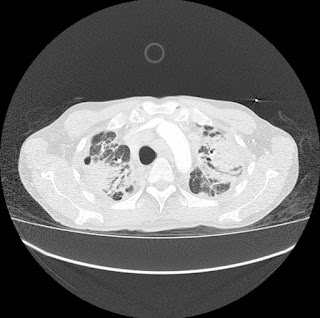

Hombre de 61 años asintomático. Colonoscopia demuestra válvula ileocecal ulcerada y estenótica. No hay antecedente de Enfermedad Inflamatoria Intestinal.

Con base en lo anterior el siguiente paso a seguir es?

a) Valoración por cirugía general.

b) Iniciar tratamiento con anti-inflamatorios e inmunosupresores.

c) Biopsia bajo guía ecográfica de las lesiones focales hepáticas.

d) Repetir colonoscopia.